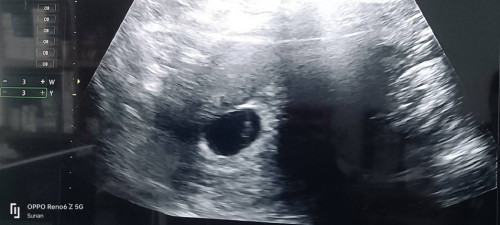

ถุงตั้งครรภ์ 6 สัปดาห์ ซาวไม่เห็นตัวเด็ก เครียดเลยค่ะ

ตั้งครรภ์ 6 สัปดาห์ค่ะ คุณหมอนัดซาวเจอถุงตั้งครรภ์ แต่ยังไม่เห็นตัวเด็ก คุณหมอบอกว่าเห็นถุงไข่แดงข้างใน ตอนนี้แม่เครียดกลัวเปนท้องลม ตอนแม่ๆ6สัปดาห์ ซาวเปนแบบไหนกันบ้างคะ

ของเราตอน 6 สัปดาห์ น้องก็เป็นถุงรีๆ ไม่เจอไข่แดง ไม่เจอน้อง ไม่เห็นหัวใจเต้นเหมือนกันเจ้า เพิ่งเห็นหัวใจเต้นตอน 8 สัปดาห์ (เรารอบเดือน 40 วัน ไข่น่าจะตกช้าด้วยค่ะ)

6สัปดาห์ เหมือนกันคะเเต่ซาวผ่านหน้าท้องจะไม่เห็นน้องคะเจอเเต่ถุงตั้งครรภ์เเนะนำซาวผ่านช่องคลอดคะ เห็นน้องเเน่นอนคะเเต่ตัวน้องจะเล็กมากคะ ไม่ต้องเครียดนะคะ